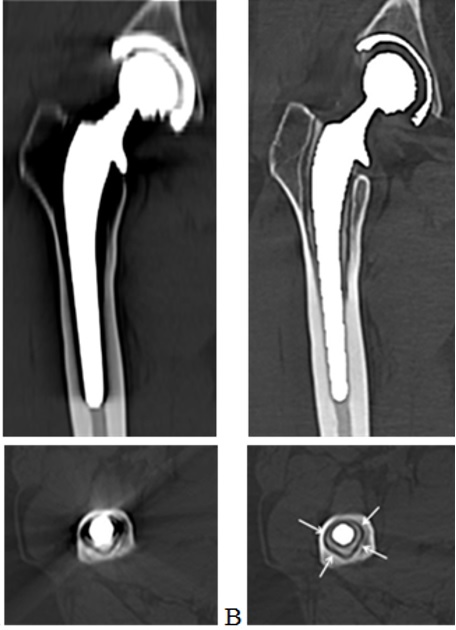

Hình 5. Hình ảnh chụp CLVT khớp háng phải nhân tạo.

A: Hình ảnh chụp CLVT thường quy;

B: Hình ảnh chụp CLVT 512 dãy sử dụng công nghệ giảm nhiễu ảnh kim loại